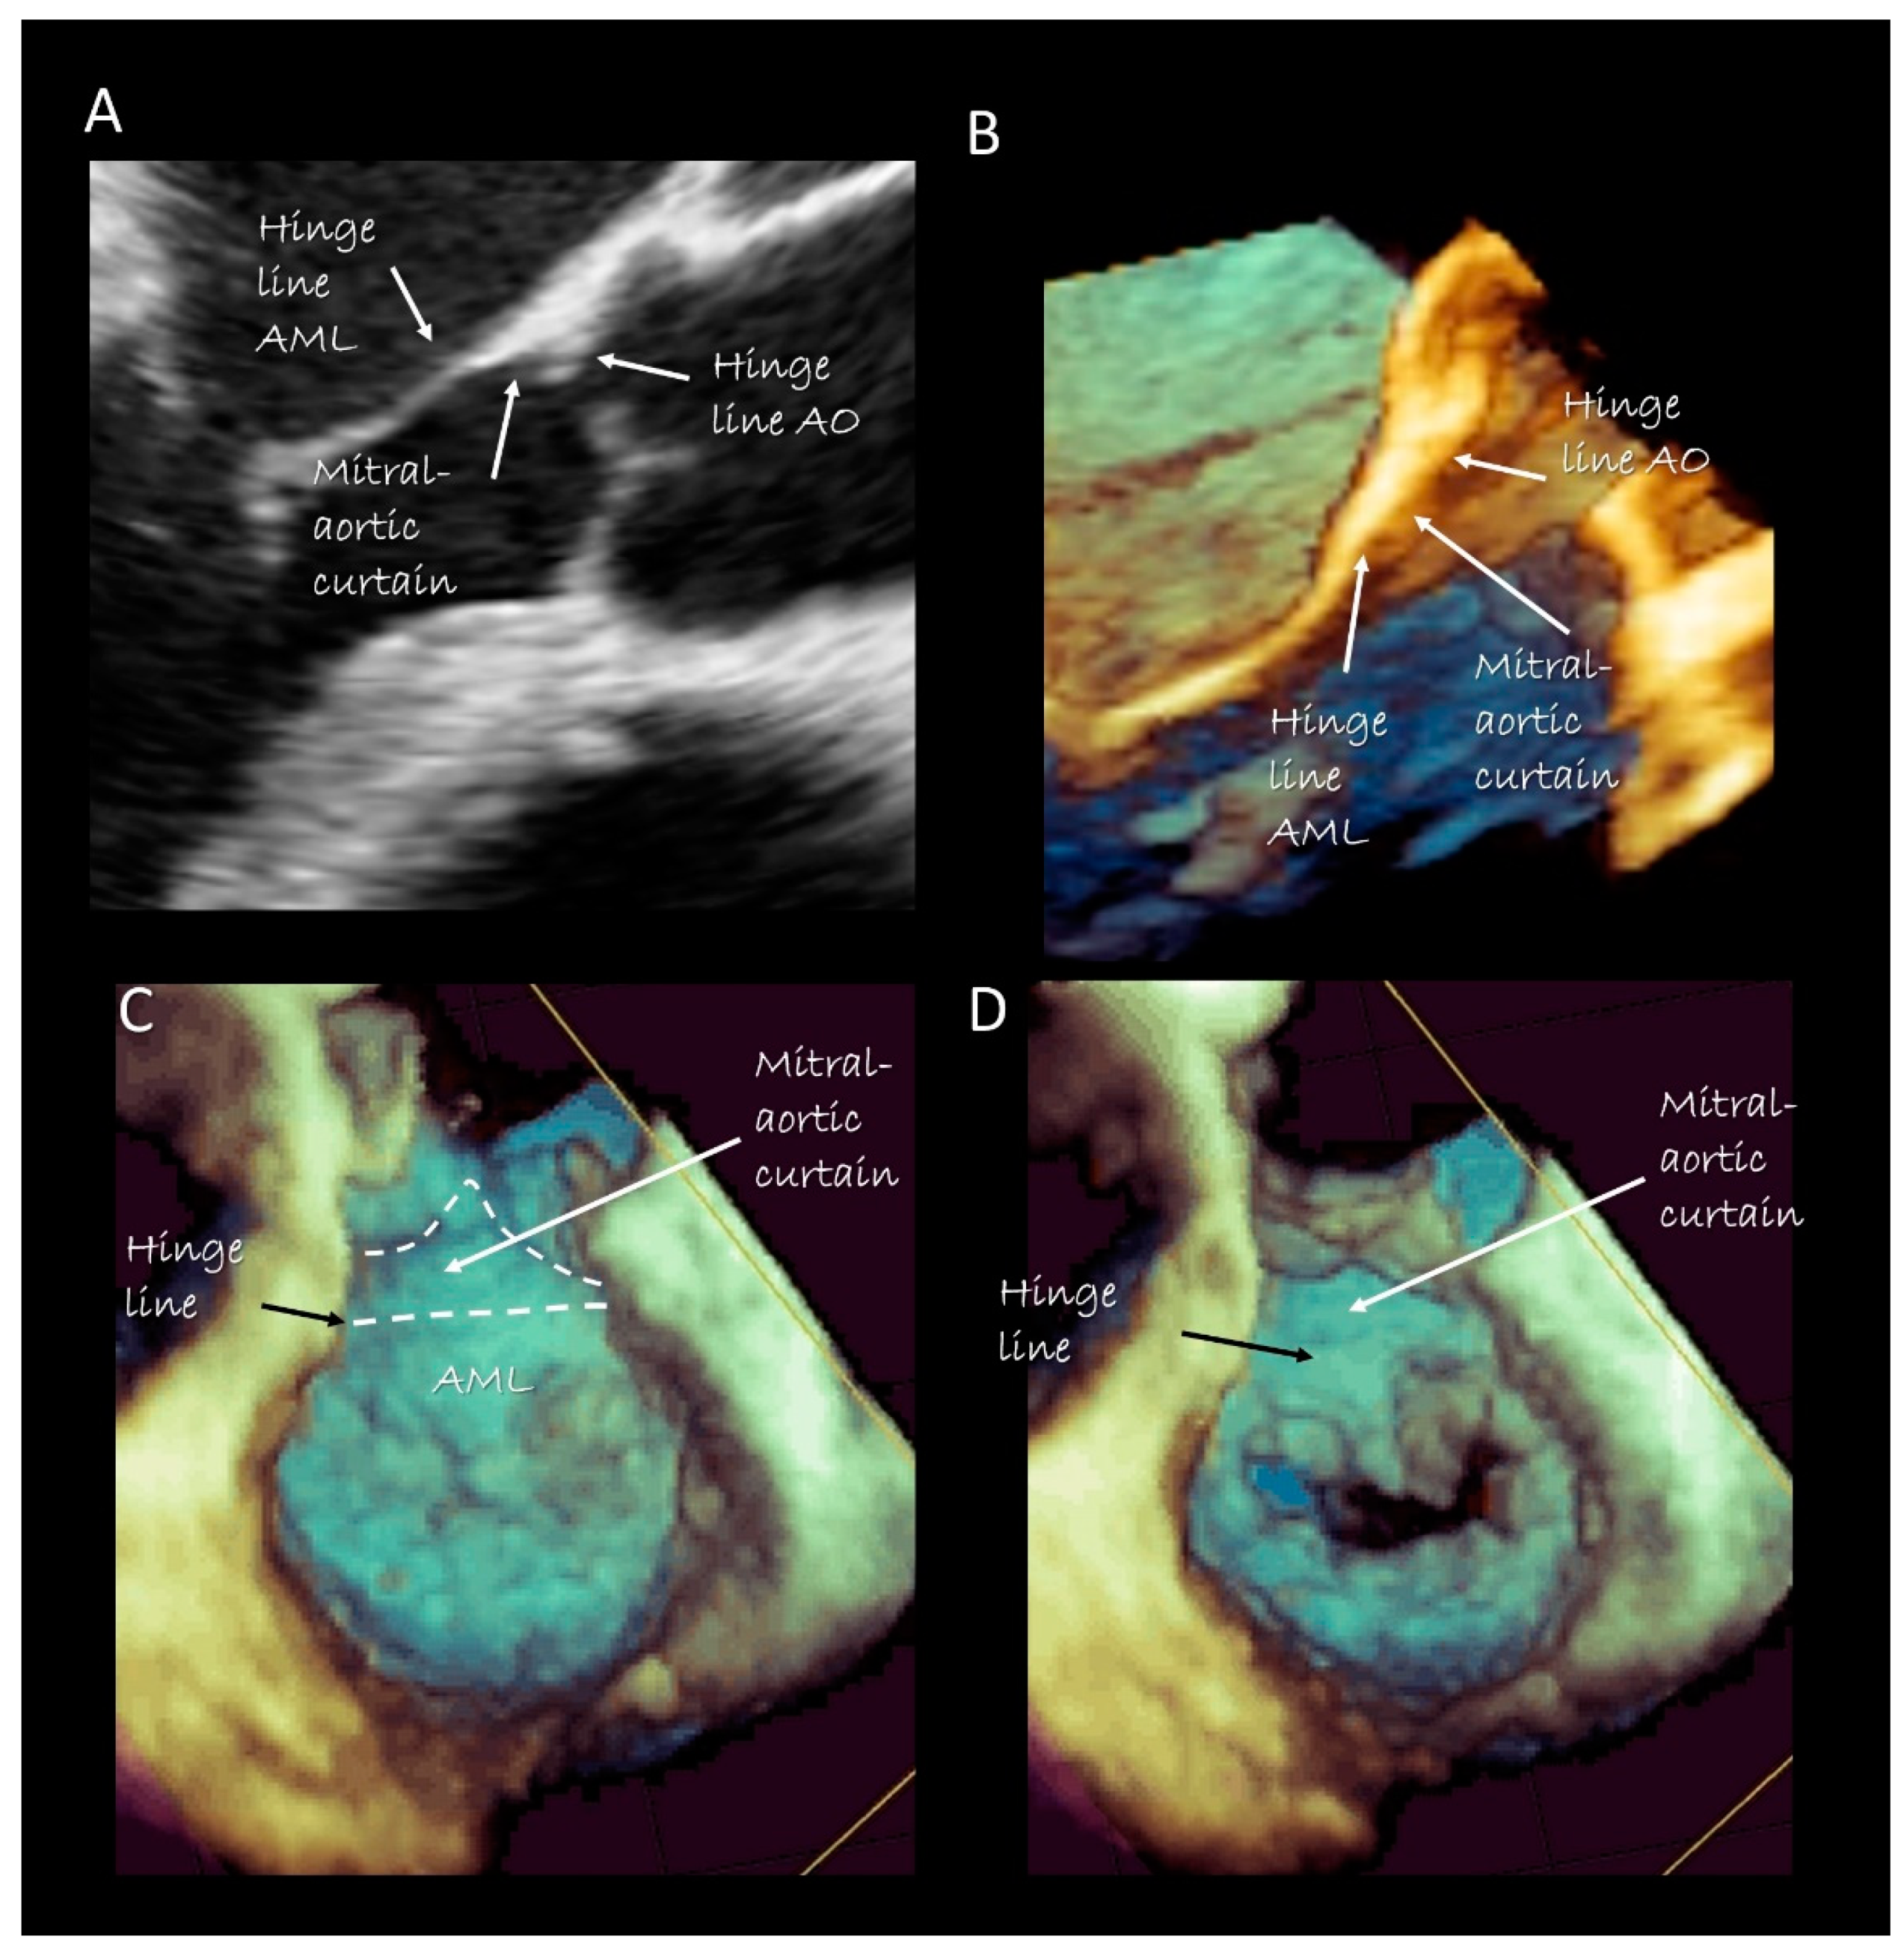

Figure 4.

Two-dimensional (A) and three-dimensional (B) TEE cross-section long-axis view showing the hinge line of anterior mitral leaflet (AML), the hinge line of the aorta (AO) and in between the mitral aortic curtain. (C,D) 3D TEE from a ventricular perspective in systole (C) and in diastole (D), showing the mitral–aortic curtain in “en face” view.

The anterior segment of the MA is actually made up only by the hinge line of the anterior mitral leaflet (AML). In its ventricular aspect, this hinge line continues with the mitral–aortic curtain, a strip of fibrous tissue delimited medially and laterally by two robust fibrous nodules called trigones. The mitral aortic curtain gradually merges with the left interleaflet triangle (ILT) located between the non-coronary and left coronary sinus. However, there is marked normal variation in this relationship depending on the normal variation seen in the rotational position of the aortic root [15]. Since there are no anatomical boundaries between the ventricular surface of the AML, the mitral–aortic curtain and the aortic ILT, these components should be considered as a single structure. From an atrial perspective the hinge line of the AML is in direct continuity with the atrial wall.

Imaging Techniques

Cross sections obtained by 2D TTE and TEE, CMR and CT perfectly portray these anatomical details (Figure 2). Three-dimensional TEE from an overhead perspective shows unique images of the entire hinge line of leaflets. Notably, in the cross section, the fibrous posterior annulus should appear as a fibrous nodule. It must be emphasized that none of the above-mentioned techniques is capable of visualizing this fibrous nodule as a distinct structure. Thus, the only means to visualize the posterior annulus is through histological specimens. The absence of a rigid “C-shaped” semi-annulus facilitates the sphincteric-like contraction. Those segments of posterior leaflet attached directly on ventricular myocardium freely follow contraction and relaxation of left ventricle (Figure 3). CMR shows that from the atrioventricular groove, the adipose tissue (AT) penetrates deeply up to the base of posterior leaflet. This “intrusiveness”, along with the fibrous skeleton of the heart, may contribute to the electrical insulation between the atrial and ventricular musculature and may provide a mechanical protection to coronary artery buffering and to the torsion induced by arterial pulse and myocardial contraction. Cross-sectional planes 2D/3D TEE, CT scan and CMR show as the hinge line of the anterior leaflet is more apically displaced than the hinge line of aortic leaflet. The space between the two hinge lines is occupied by the above-mentioned mitral–aortic curtain (Figure 4A,B). Three-dimensional TEE permits visualizing the mitral–aortic curtain from an “en face” perspective showing as the base of the AML, its hinge line, the mitral–aortic curtain and the ILT, which appear as a single area with no boundaries (Figure 4C,D).